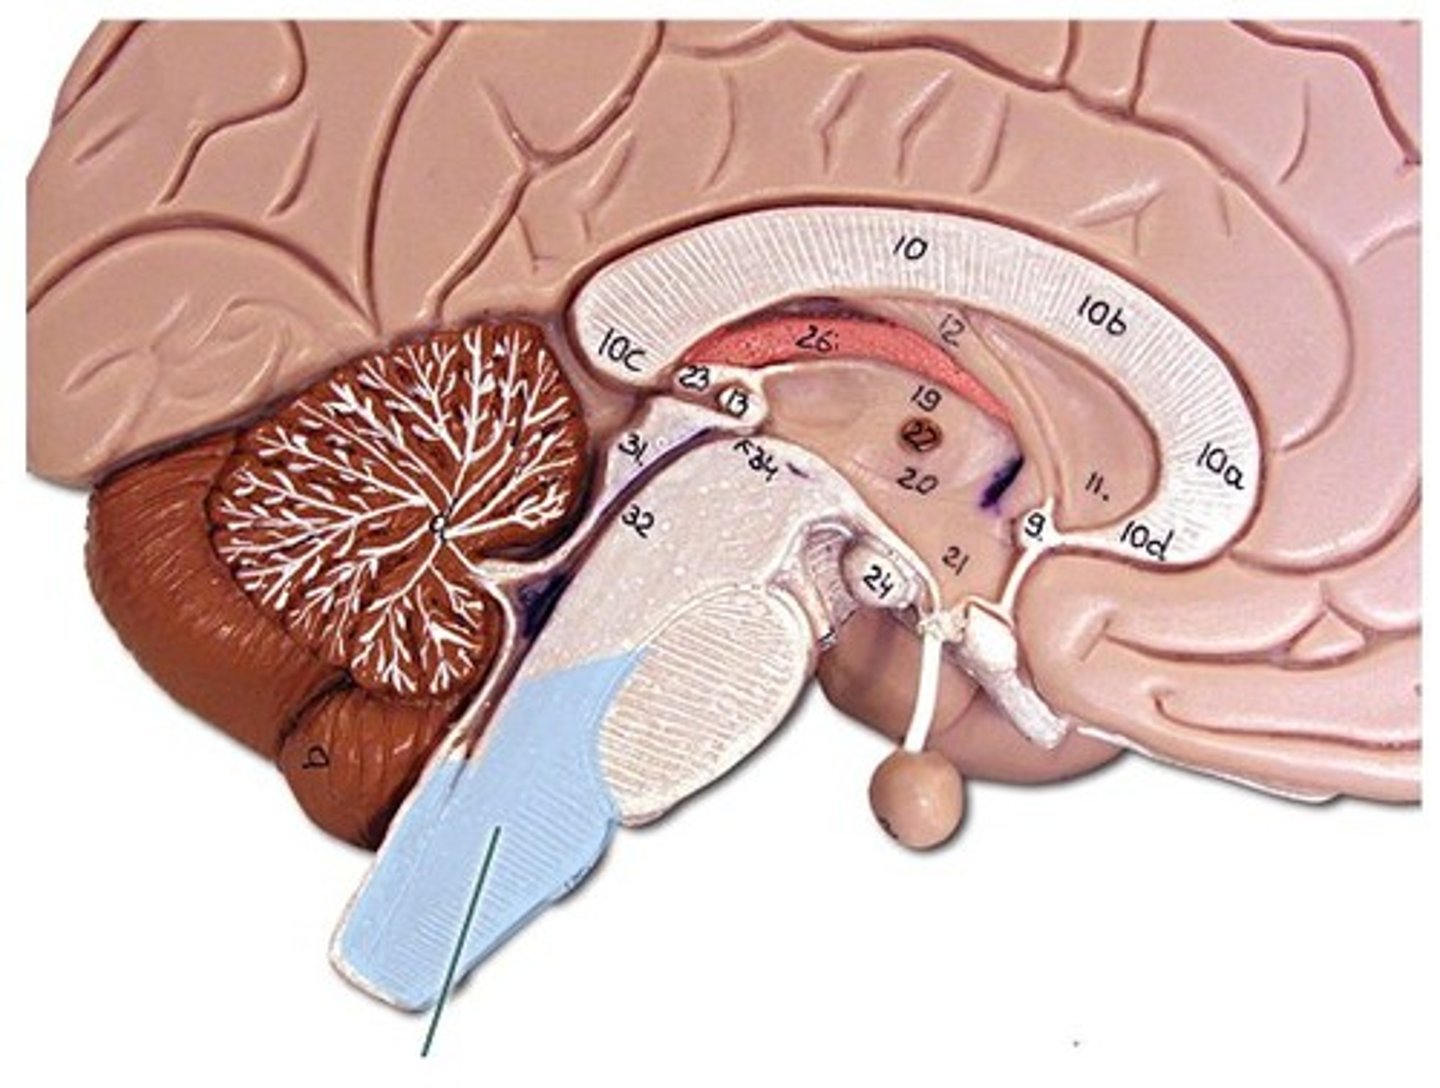

Corpus callosum

Fornix

Septum pellucidum

Pineal Gland

Arbor Vitae

Cerebellum

pons

Pituitary Gland

Fourth Ventricle

Intermediate mass of the thalamus

spectum pellucidum

Thalamus

Hypothalamus

Cerebral Aqueduct

Medulla Oblongata